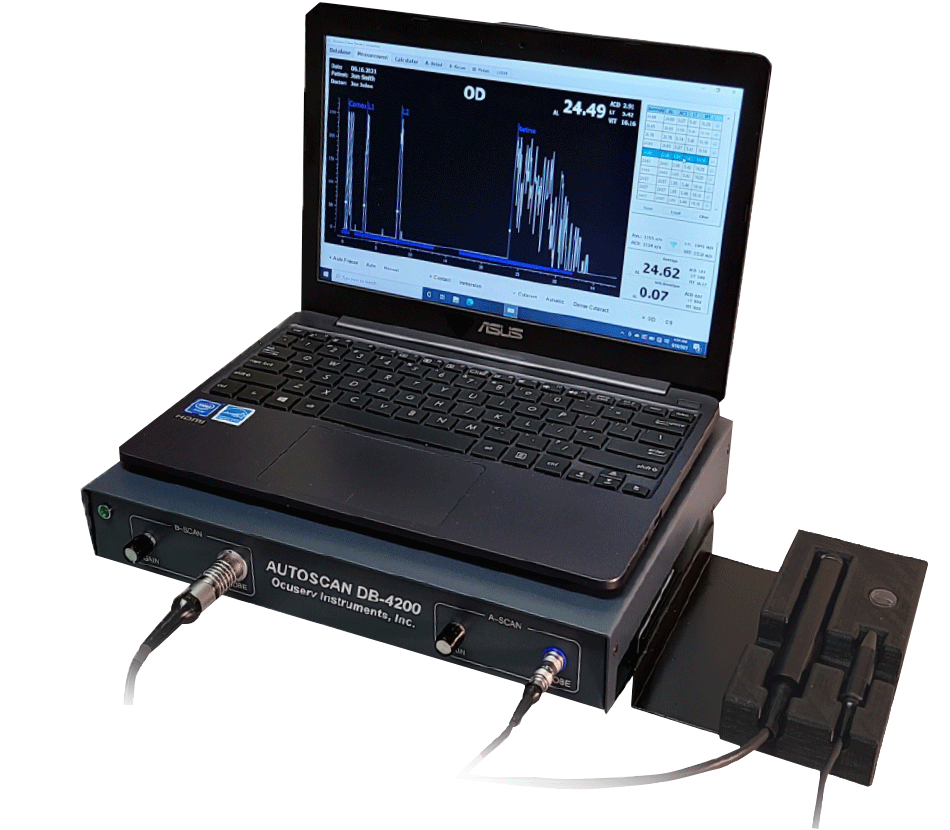

A-Scan

- The A-Scan part of the system performs intraocular distance measurements in seconds using contact or immersion method in either automatic or manual mode.

B-Scan

- Exceptional signal to noise ratio yields a deep penetration while maintaining high resolution image.

- 10 MHz transducer and 55 degrees of viewing angle with 256 scan lines produces a high quality sonogram.